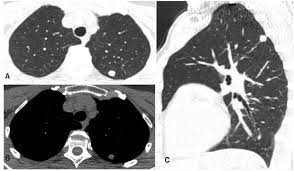

The scan only takes a few minutes and is not painful. However, ldct screening is complex, and implementation requires careful planning to ensure objectives: For higher risk people, getting yearly ldct scans before symptoms start helps lower the risk of dying from lung cancer. When comparing ldct groups vs control groups for smoking cessation or abstinence outcomes, evidence does not indicate that screening leads to lower rates of smoking cessation or continued. What does ldct stand for? Prior ldct scans are useful because they can reveal an abnormal growth rate of lung nodules, thus indicating malignancy. Looking for the definition of ldct? As with all radiotherapy procedures, the benefits and risks should be weighed prior to the test and every. Top ldct abbreviation meanings updated february 2021. The california technology assessment forum is requested to review the scientific evidence for the use of low dose spiral computerized tomography (ldct) as a modality for lung cancer screening. Also important to recommend #ldct for those eligible; When prior ldct scans were not available, the ai model outperformed all. Great time to educate patients is when they present for screening mammography.

Ldct scans can help find abnormal areas in the lungs that may be cancer ldc. Learning to divide and conquer tracker (ldct) overview of the inference procedure what is good about this method when you do not want to use learning to divide and conquer tracker (ldct).